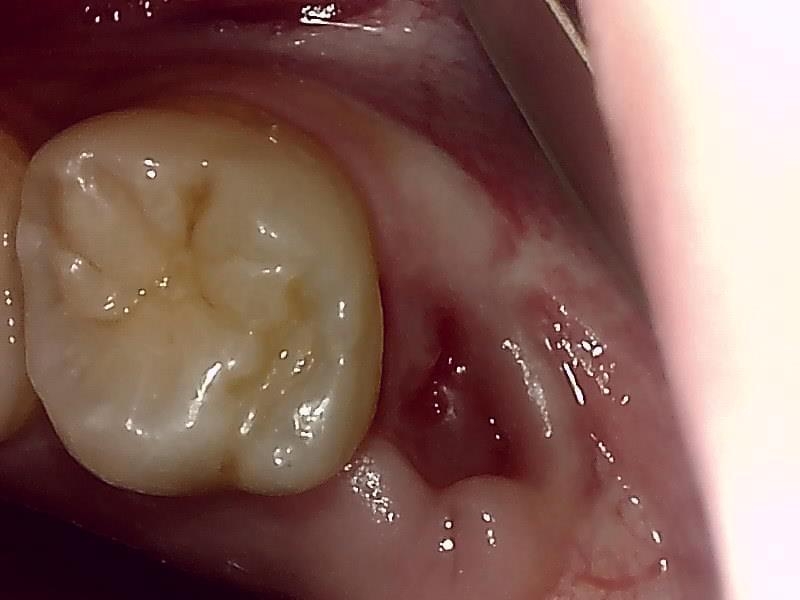

(左上)抜歯窩

治癒

当院では、傷口は最小限に行います。

親知らずのみにアプローチし歯を最小限の傷口で取り出します。

抜歯後、経過良好です。